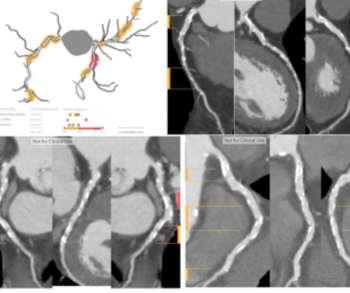

In the newly released Lung-RADS 2022 classification system for computed tomography (CT) lung cancer screening, the American College of Radiology (ACR) has noted a variety of updates including new classification criteria for atypical pulmonary cysts and airway nodules, time intervals for nodule growth and a new stepped management approach for Lung-RADS categories 3 and 4A.